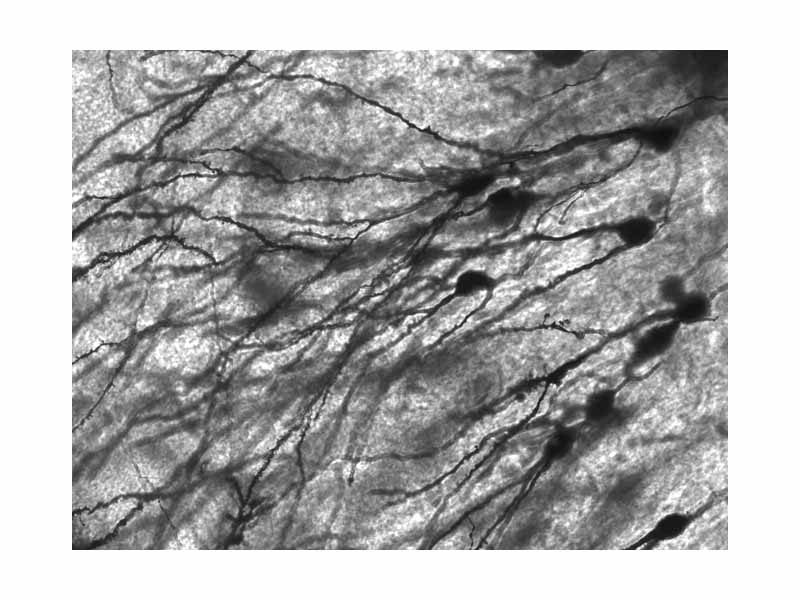

Golgi-stained neurons in human hippocampal tissue.